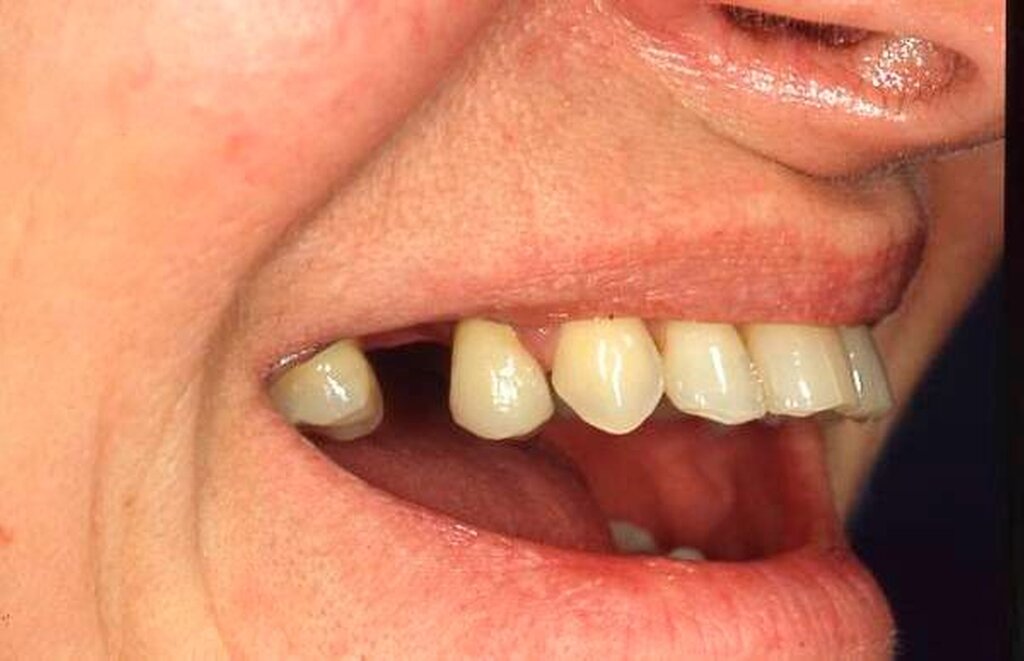

Abbildung 1a bis 1f: Direkte Überkronung im Frontzahnbereich (R1-Technik)

In den Abbildungen 1 bis 3 werden Optionen für frugale Interventionen auf restaurativem Sektor aufgeführt. Es handelt sich um direkte Vollüberkronungen im Frontzahnbereich (hier: hergestellt in R1-Technik / einphasig) (Abbildung 1), direkte Teilüberkronungen im Seitenzahnbereich (hier: hergestellt in R1-Technik / einphasig) (Abbildung 2), Reparatur-Restaurationen im Seitenzahnbereich (hier: hergestellt in R2-Technik / zweiphasig) (Abbildung 3). Technische Einzelheiten zur Vorgehensweise und den Ergebnissen sind an anderer Stelle beschrieben (Literatur siehe oben).

Am Beispiel von Abbildung 1 (stark zerstörte Zahnkrone eines Schneidezahns) kann das Prinzip der frugalen Intervention erläutert werden:

Früher wurde für die hier beschriebene Ausgangssituation folgendes Procedere gewählt:

Wurzelkanalbehandlung des vitalen Zahns als Voraussetzung für eine Stiftversorgung

Einsetzen eines Wurzelkanalstifts

Einsetzen einer indirekt gefertigten Stiftkrone

Durch die Erfolge der Adhäsiv- und Komposittechnik kann heute folgendermaßen vorgegangen werden:

Verzicht auf Wurzelkanalbehandlung / Erhaltung der Vitalität des Zahns

Verzicht auf Wurzelkanalstift

direkte minimalinvasive Kompositkrone (Verzicht auf indirekte Vorgehensweise)

Die potenziellen medizinischen und ökonomischen Vorteile dieser frugalen Intervention sind vielfältig:

Schonend: Die oralen Strukturen werden geschont und die Versorgung ist hinreichend stabil. Durch den Verzicht auf Wurzelkanalstifte wird das Wurzelfrakturrisiko reduziert. Zudem können Material-, Geräte- und Personalressourcen aus Praxis und Techniklabor, die beim klassischen Vorgehen anfielen, reduziert werden.

Bezahlbar: Hier ist anzumerken, dass die Kosten unter anderem von der zahnärztlichen Expertise abhängig sind: Zahnärzte, die mit direkten Restaurationen große Erfahrung haben, können zügiger und mit besserem Erfolg arbeiten als Kollegen mit geringerer Erfahrung auf diesem Gebiet; die Behandlung ist gleichwohl anspruchsvoll und deshalb nicht „billig“. Eine direkte Vorgehensweise kann, muss aber nicht automatisch zeit- und kostensparender sein als eine Versorgung mit indirekt hergestellten Werkstücken.

Gut genug: Ästhetische Feinheiten lassen sich bei direkten Restaurationen nicht immer in gleicher Perfektion einarbeiten wie bei indirekt gefertigten Kronen, auch die Stabilität des Hochglanzes lässt bei einigen Kompositpräparaten noch zu wünschen übrig. Andererseits erlauben die direkten Verfahren inzwischen mitunter sehr flexible Vorgehensweisen, die sich auch mit Farb- und Formkorrekturen von Zähnen kombinieren lassen. Die Erwartungen eines großen Teils der Patienten werden hinreichend erfüllt und die Nutzen-Risiko-Relationen wie auch die Aufwand-Kosten-Relationen erscheinen – wenn auch nicht durchgängig – so doch zumindest in vielen Fällen günstig.